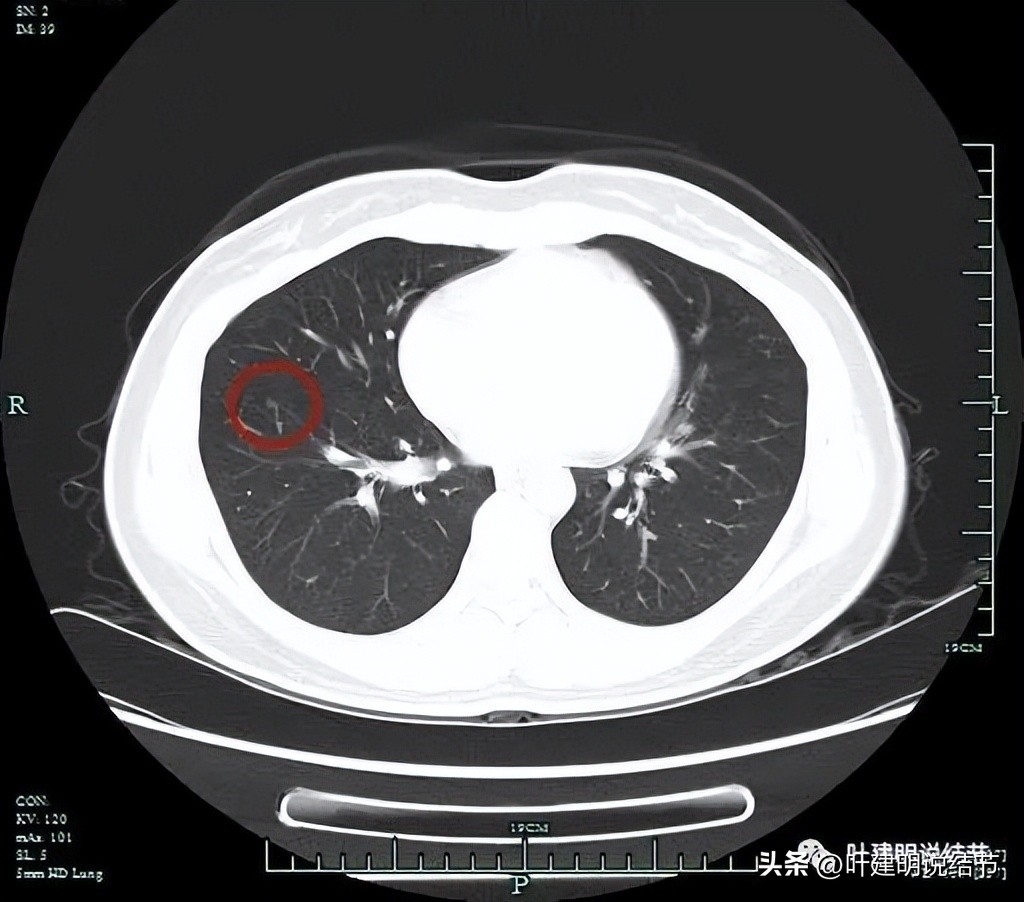

薄层影像:

薄层见病灶1轮廓较清,边缘似乎有少许细毛刺,考虑不典型增生可能性较大,但近期风险低,能随访。

薄层见病灶2有胸膜牵拉、空泡征以及瘤肺边界清,表面有轻微分叶,灶内有实性成分,考虑恶性的,浸润性腺癌可能性大,至少微浸润性腺癌。需要尽早手术治疗为宜。

薄层见病灶3其实是实性的,而且非常光滑,密度过高,考虑肺内淋巴结或纤维增生结节可能性大。